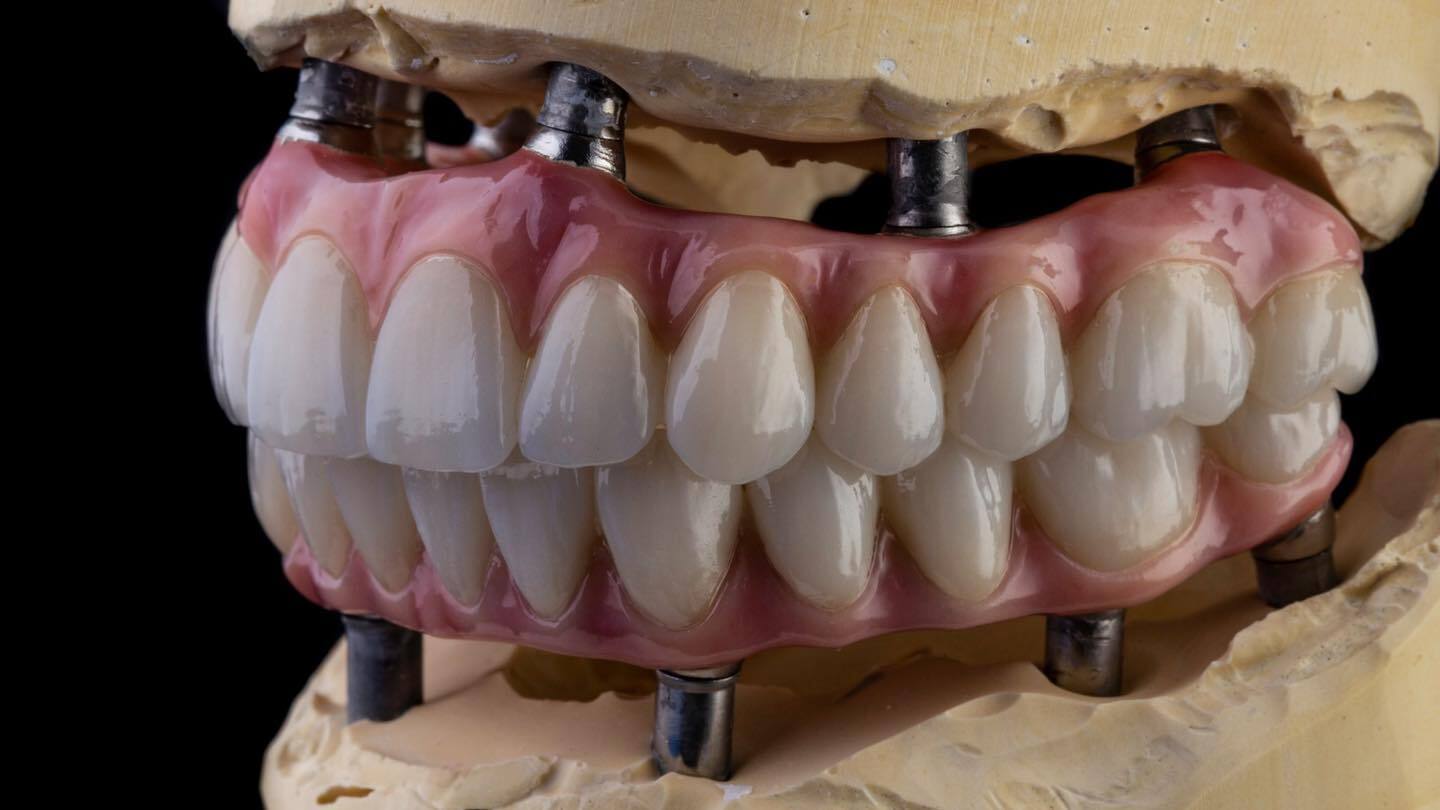

Un paziente che monta la Linea Superior

Linea Superior è un'arcata dentale sviluppata dal Dr Palmas, disegnata a New York e prodotta in Moldavia.

La linea Dentale più avanzata al mondo 100% Digitale, fatta al Computer, e prodotta roboticamente. Possibile essere riparata a distanza, grazie allo Stock in Cloud delle forme dei denti trasmissibili al centro di rigenerazione dentale.

Dipartimento di Biomimetica

Sezione Ricostruttiva Bocca bionica

• Denti progettati al Computer: per poterli realizzare identici ai denti naturali

• Finalizzati a Mano: simulazione ultrarealistica dei tessuti perduti

• Non solo Impianti aa soprattutto Denti: I Denti sono la parte che nel tempo viene sottoposta ad Usura, ecco perché è importante realizzare denti sofisticati